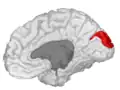

![]() Medial surface of left cerebral hemisphere. (Cuneus visible at left in red.) | |

Position of cuneus(red) of left cerebral hemisphere.